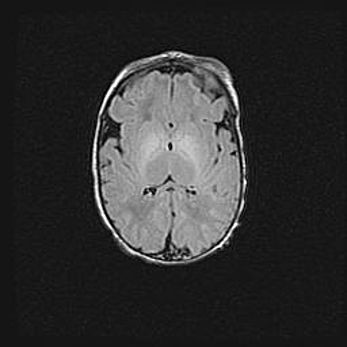

Наружная гидроцефалия с возможной атрофией височных областей.

Возраст: 28 дней

Вес: 3670 г

Пол: мужской

Окружность головы: 38 см

Срок гестации: 40 недель

Гидроцефалия головного мозга у новорожденных – это заболевание, которое характеризуется скоплением избыточного количества спинномозговой жидкости в желудочковой системе головного мозга в результате затруднения её перемещения от места выработки к месту поглощения в кровеносную систему или вследствие нарушения абсорбции. При открытой наружной форме гидроцефалии у новорожденных расширяются и переполняются субарахноидные пространства.

При нормотензивных  формах,  которые,  как  правило,  являются  следствием  перенесенных ишемических  повреждений  паренхимы  мозга,  возможно  сочетание микроцефалии  с нормотензивной гидроцефалией. В основе данных изменений лежит атрофия больших полушарий с преимущественной  локализацией  в  лобно-височных  областях.